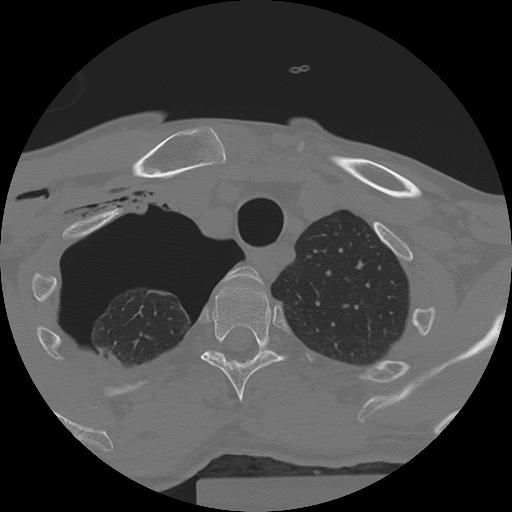

11 HUESO,,Axial,2.0,HUESO,,